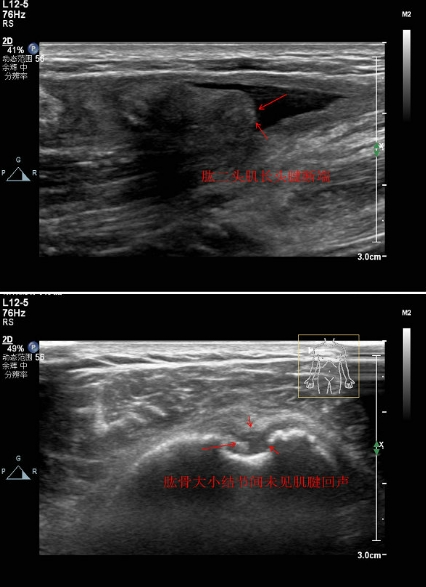

4.肱二頭肌長頭腱斷裂